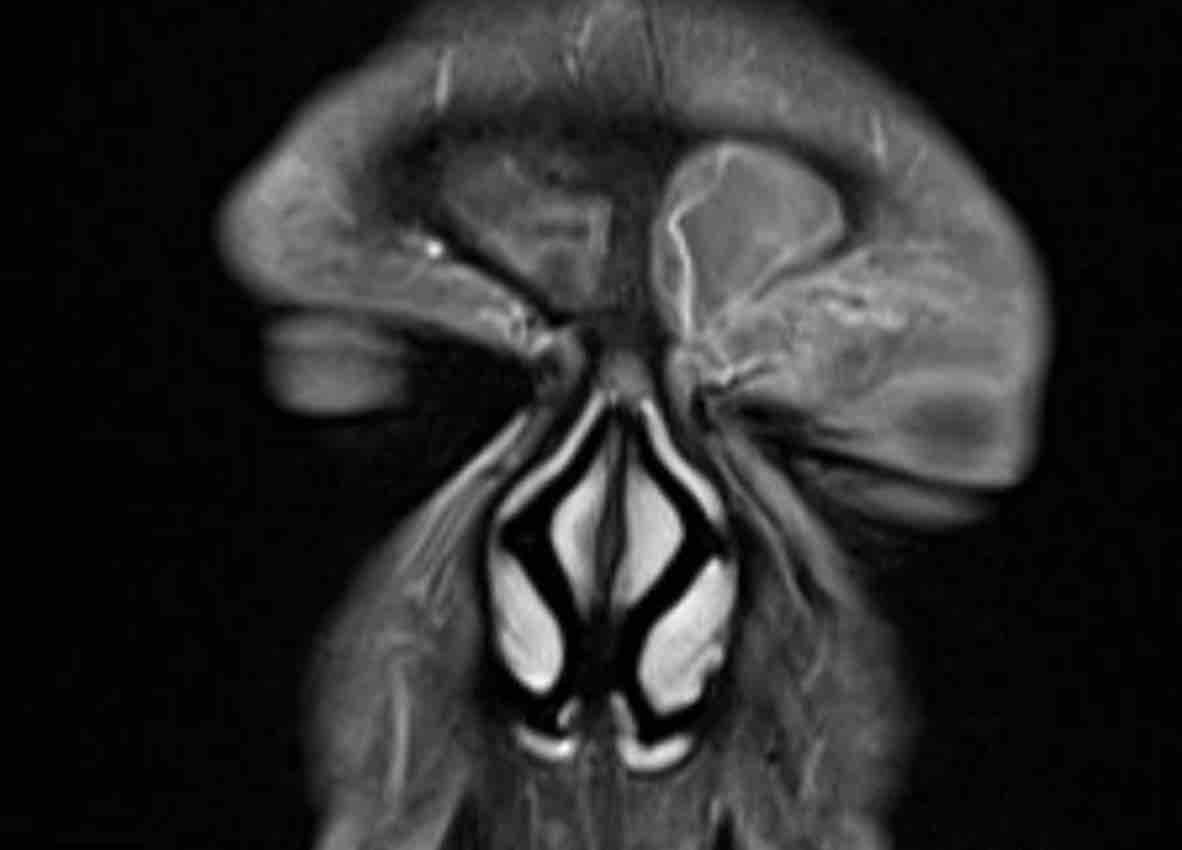

Tiếp tục với MRI…

Trên các hình ảnh STIR này, có thể thấy sự khác biệt về cường độ tín hiệu giữa xoang hàm và xoang sàng bị tắc nghẽn (mũi tên đen) và khối u (mũi tên trắng).

Ở bệnh nhân nang nhầy, toàn bộ tổn thương sẽ có cùng cường độ tín hiệu, khác với trường hợp này.

Trên hình ảnh khuếch tán, tổn thương có tín hiệu cao trên b1000.

Trên bản đồ ADC, tổn thương có tín hiệu rất thấp, thậm chí thấp hơn cả mô não, gợi ý tình trạng hạn chế khuếch tán rõ rệt.

Điều này có nghĩa là chúng ta đang đối mặt với một khối u tăng mật độ tế bào.

Đây là dấu hiệu cảnh báo thứ ba.

Trên CT, có thể có ấn tượng rằng khối u cũng xâm lấn xoang trán (mũi tên đen).

Tuy nhiên, trên MRI, chúng ta có thể thấy rõ ràng rằng xoang trán chỉ bị tắc nghẽn và có cường độ tín hiệu cao hơn (mũi tên trắng) so với khối u ở các xoang sàng (mũi tên vàng).